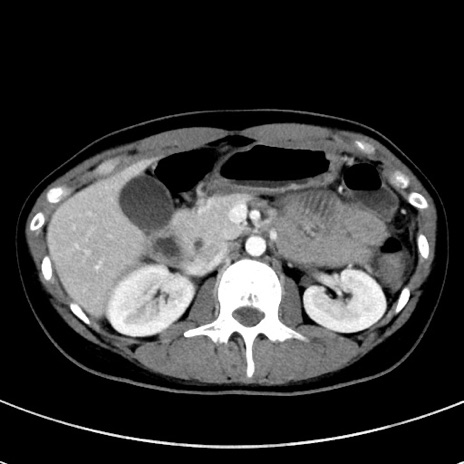

症例17(横断像)

【症例】20歳代女性

【主訴】嘔吐、下腹部痛

【現病歴】昨日夕食後に嘔吐し下腹部痛が出現。本日になっても嘔吐持続し改善しないため来院。

【身体所見】意識清明、BT 37.2℃、BP 108/67mmHg、腹部:平坦、やや硬、下腹部正中から右にかけて圧痛あり、反跳痛軽度あり、tapping pain(+)。

【データ】WBC 13600、CRP 14.94